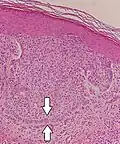

Палисады при базально-клеточной карциномые- Палисадные структуры при шваноме

Микрофотография амелобластомы с характерным палисадом и звездчатым ретикулумом